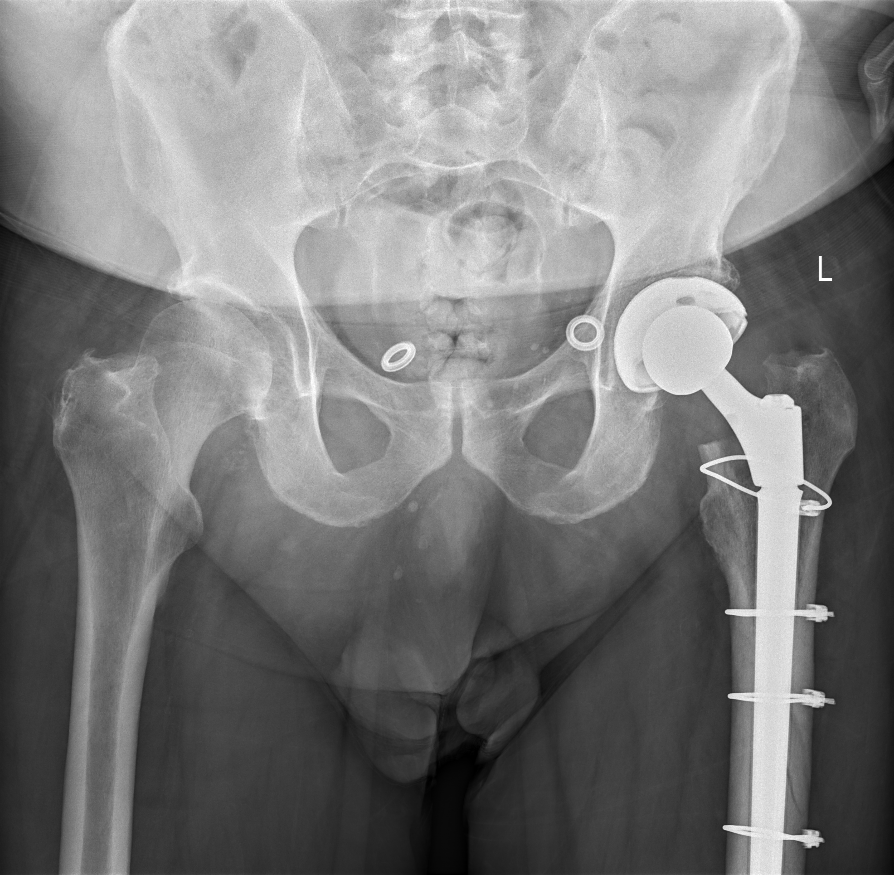

Example of Revision Total Hip Replacement

Revision Hip Replacement

A revision total hip replacement, demonstrating cables to fix a femoral fracture